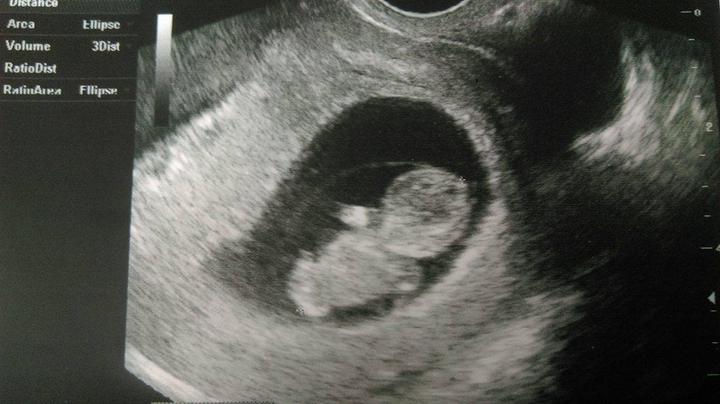

Zítra konečně na screening 🙂 těším se až přítel uvidí toho našeho drobečka 🙂 a že bude vše v pořádku 🙂 byl jste někdo v plzni v Černicich? 🙂 jak jste byli spokojeni? 🙂